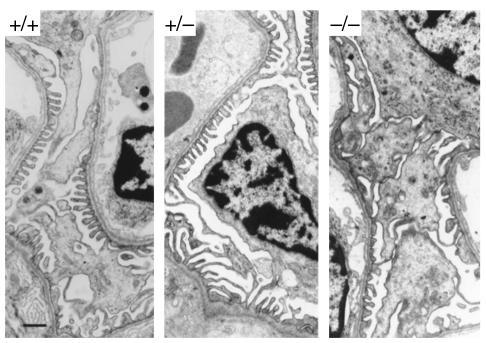

Transmission electron micrographs showing glomerular capillary loops from Ptpro+/+, Ptpro+/–, and Ptpro–/– mice, revealing broader foot process structure in the Ptpro–/– mice. Bar, 1 μm.